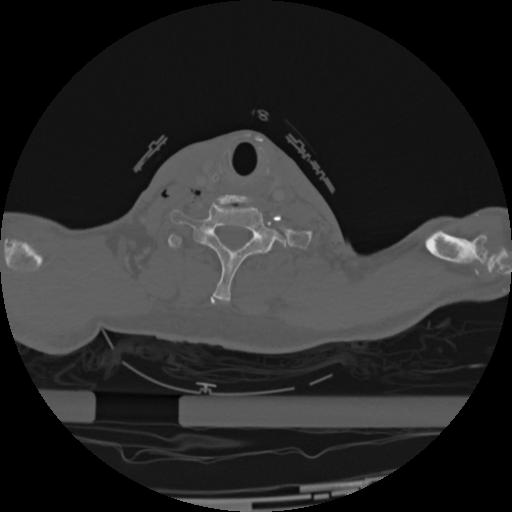

22 ANGIO,CE,Vol,0.5,ANGIO,,